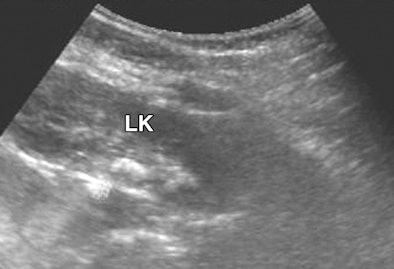

| Eight-month-old female infant with two-day history of anuria and fever who had been exposed to infant milk formula contaminated with melamine and cyanuric acid for eight months. Sonography image of left kidney (LK) shows hyperechoic crescent-shaped calculus in renal pelvis without hydronephrosis. All images reprinted with permission from the American Journal of Roentgenology. |

Diagnostic imaging displayed calculi formation of the urinary tract, with calculi varying greatly in size and shape, according to the authors. Fourteen patients had multiple calculi and 12 patients had bilateral calculi. A total of 51 calculi were identified.

The 37 renal calculi observed were oval, staghorn, or punctiform and were not measured because they varied greatly in size and shape. The 14 ureteral calculi were oval in shape and averaged 8 x 5 mm in size, with a range of 4 x 3 mm to 11 x 8 mm.